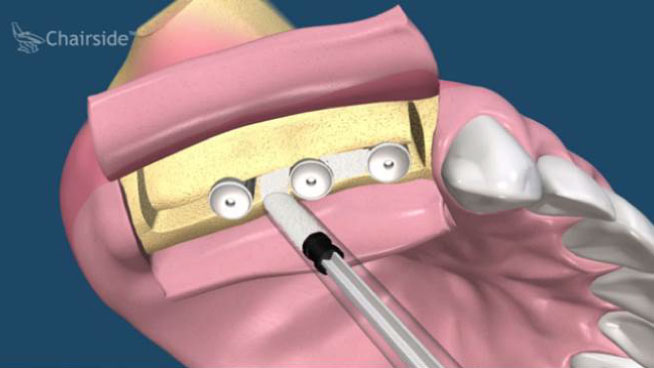

All-on-Fou/Six

近年來由於人工植牙的技術普及,患者大都知道植牙可做固定式假牙,但同樣的有時患者因為身體、經劑因素等受限,也可以考慮植入幾支人工植牙,再完成固定可撤式活動義齒,這樣可讓活動式假牙的固定性有效加強。通常上顎可用6支植體,下顎則4-5支植體固定,如需更穩定的受力,亦可再增加植體數目。(圖52-55)

圖52

圖53

圖54

圖55

參考病例: 固定式植牙牙橋&固定可撤式活動義齒